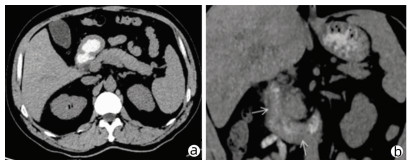

Acute pancreatitis caused by a hematoma in the duodenal wall: A case report

2022, 38(3): 639-642. DOI: 10.3969/j.issn.1001-5256.2022.03.029

Abstract(1350) HTML (248) PDF (3475KB)(62)

Abstract: